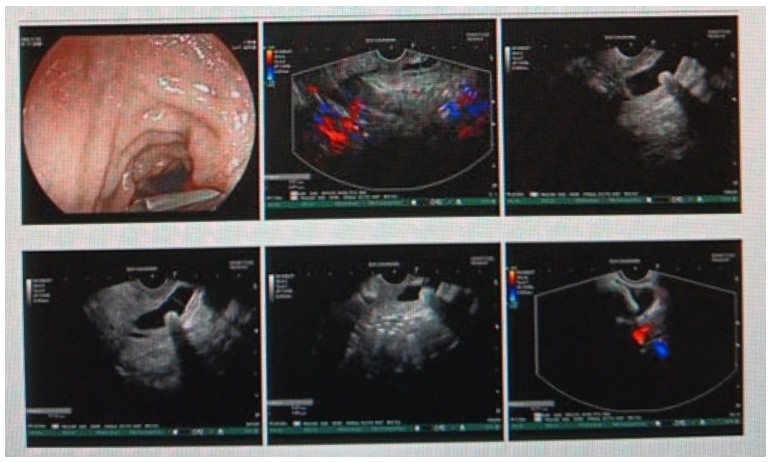

消化內(nèi)科肝病亞專(zhuān)科團(tuán)隊(duì)詳細(xì)討論,分析患者情況后,取消了周女士的肝穿刺活檢檢查,建議患者先行超聲胃鏡下膽胰掃查。在內(nèi)鏡醫(yī)師第三只眼——超聲胃鏡的掃查下,發(fā)現(xiàn)引起周女士肝功能受損的罪魁禍?zhǔn)?/span>原來(lái)是膽總管末端結(jié)石!伍友興主任醫(yī)師帶領(lǐng)團(tuán)隊(duì)給予患者行ERCP下取石后,周女士未再出現(xiàn)腹痛,肝功能恢復(fù)正常。

張丹霞主任醫(yī)師介紹,超聲內(nèi)鏡通過(guò)胃十二指腸自然腔道,可以將探頭貼近相應(yīng)的位置,近距離的觀察胰腺及膽道系統(tǒng),準(zhǔn)確捕捉到直徑小于5毫米的胰腺異常病灶及膽道系統(tǒng)病灶。而體表B超常受皮膚、脂肪或腸道氣體干擾。CT或磁共振檢查只能提供靜態(tài)圖像,且對(duì)膽胰管陰性結(jié)石或是未引起明顯膽管梗阻性的結(jié)石檢查有局限性,因此對(duì)于有輕微腹痛合并肝功能受損的患者,建議常規(guī)行超聲胃鏡下膽胰掃查。超聲胃鏡、腹部彩超、腹部CT、腹部MRI同為診斷膽管細(xì)微病變的四架馬車(chē),在膽總管結(jié)石診斷方面,超聲胃鏡膽胰掃查同ERCP一樣,是敏感性高、特異性強(qiáng)的診斷方法。超聲胃鏡發(fā)現(xiàn)可疑病變,可以完成穿刺活檢,還可行囊腫穿刺引流、膽管減壓、消融術(shù)等。